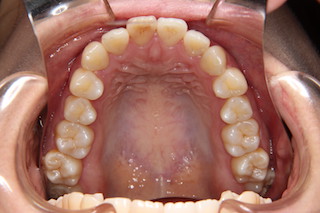

上顎・・虫歯の殆ど無い綺麗な歯です。ですから出っ歯になっているのはもったいないですね